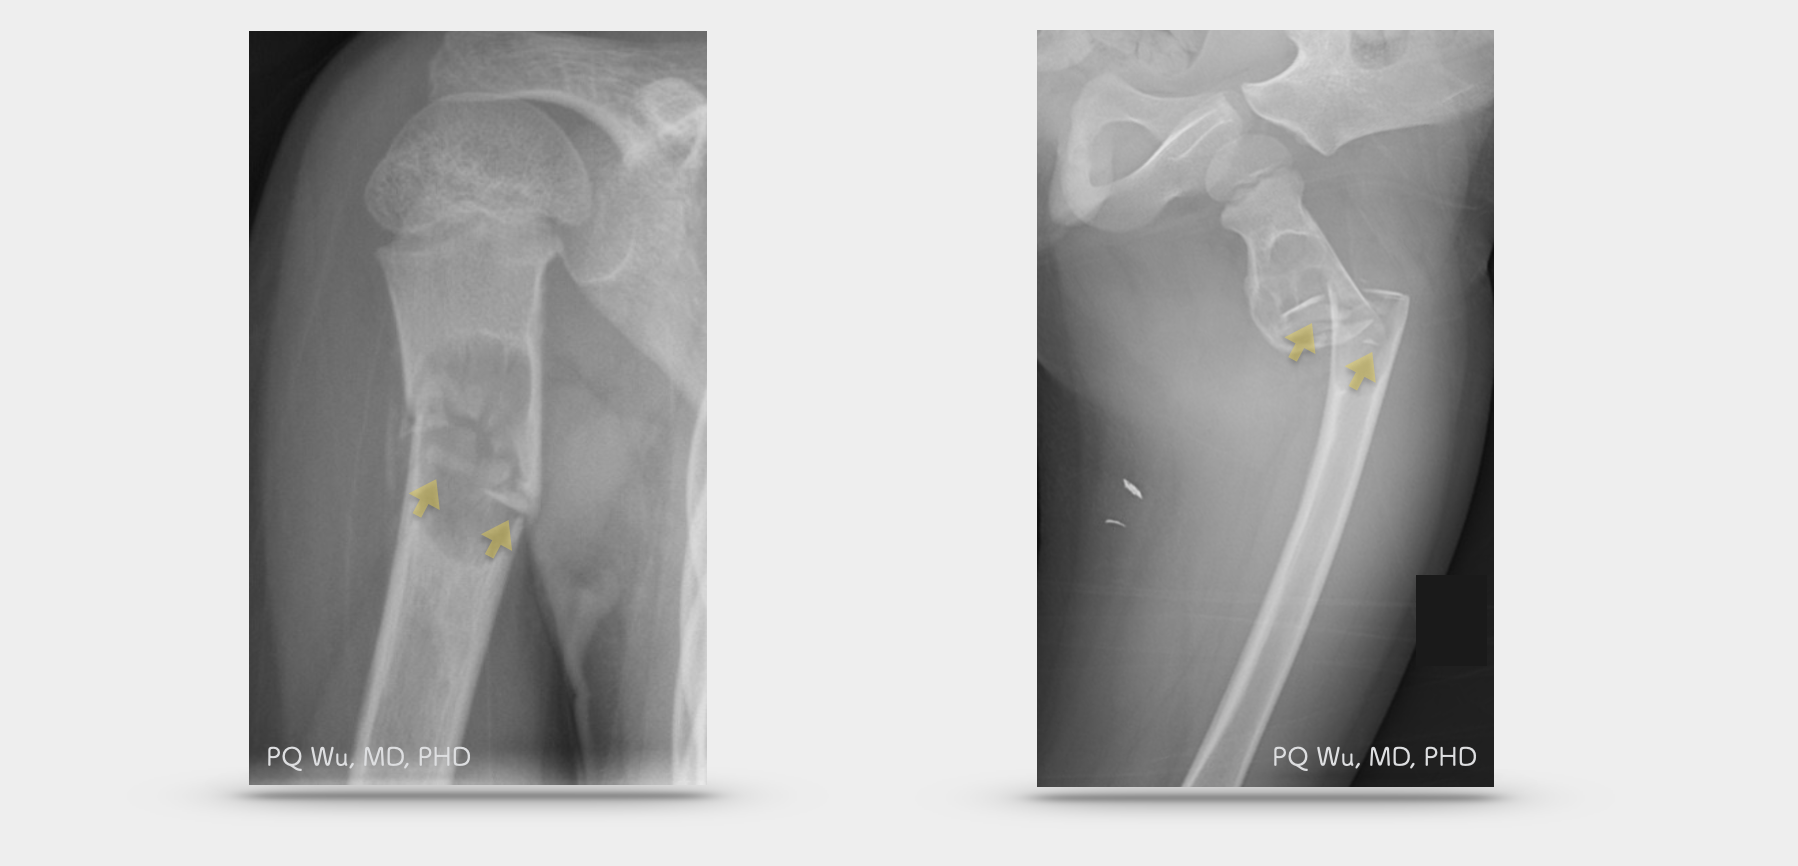

單純性骨囊腫,有一個相當特別的現象,就是原本生長幹骺端之腫瘤,會隨著病患年齡的增長,骨頭持續的長『高』,而被漸漸的從幹骺端被新長出的骨頭『推到』骨幹處。

病患年紀輕時,單純性骨囊腫生長在幹骺端。(上圖左)隨著骨頭延長,單純性骨囊腫被推到骨幹處。(上圖右)

十歲女孩,單純性骨囊腫合併病理性骨折(上圖左)。四歲男孩,單純性骨囊腫合併病理性骨折(上圖右)。